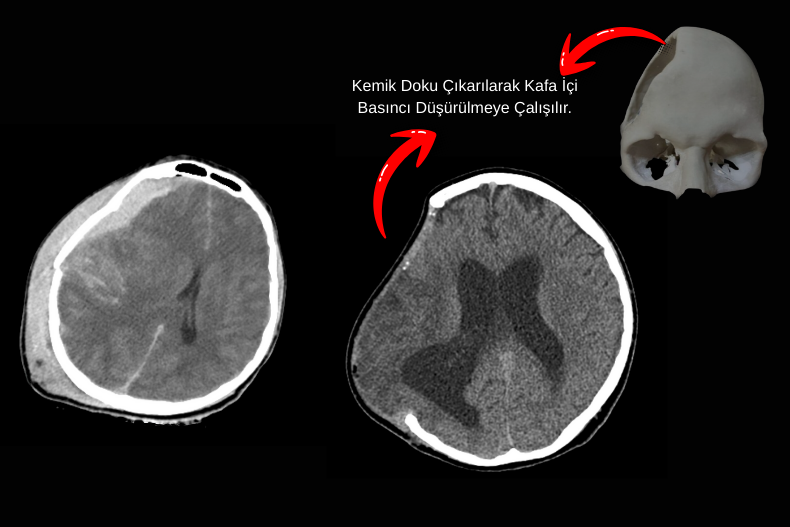

Dekompresif kraniektomi, ağır beyin travması, ağır inme ya da kontrol altına alınamayan beyin ödemi durumlarında uygulanan hayat kurtarıcı bir cerrahi yöntemdir.

Bu işlemde kafatasının bir bölümü geçici olarak çıkarılarak beynin şişmesine yer açılır ve artmış kafa içi basıncı düşürülür. Amaç, beyin sapı basısını ve geri dönüşümsüz hasarı önlemektir. Çıkarılan kemik parçası genellikle uygun koşullarda saklanır ve hasta stabilize olduktan haftalar ya da aylar sonra kranioplasti ile tekrar yerine yerleştirilir. Özellikle medikal tedaviye rağmen basıncı kontrol edilemeyen hastalarda dekompresif kraniektomi, yaşam şansını artıran önemli bir cerrahi seçenektir.